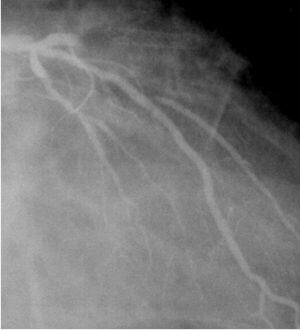

私も、約3年ほどまえに経験しました。冠危険因子は肥満のみの60歳台後半の男性

が、PS3.5mmを植え込んでから9年後、その部位にあらたに90%狭窄が発生しました

(fig-1)。治療としてはDCAを選択し(fig-2)、max 45psiで12回切除し、13mgの組織

を採取して、0%としました(fig-3)。採取された組織は、fig4にしめします。一部、

金属片もありましたが、それ以外の部分は、膠原繊維・泡沫細胞・リンパ球や一部に

石化化を認め、血栓も伴っていた との報告をもらっており、いわゆる、ステント再

狭窄の病理所見とは異なるようです。もし、病理に詳しいかたがいらっしゃいました

ら、是非、コメントください。ですから、これは、あらたに動脈硬化が生じたと考え

るべきなのだと思います。なお、DCA後のfollow-up CAGでは、再狭窄はありませんで

した。